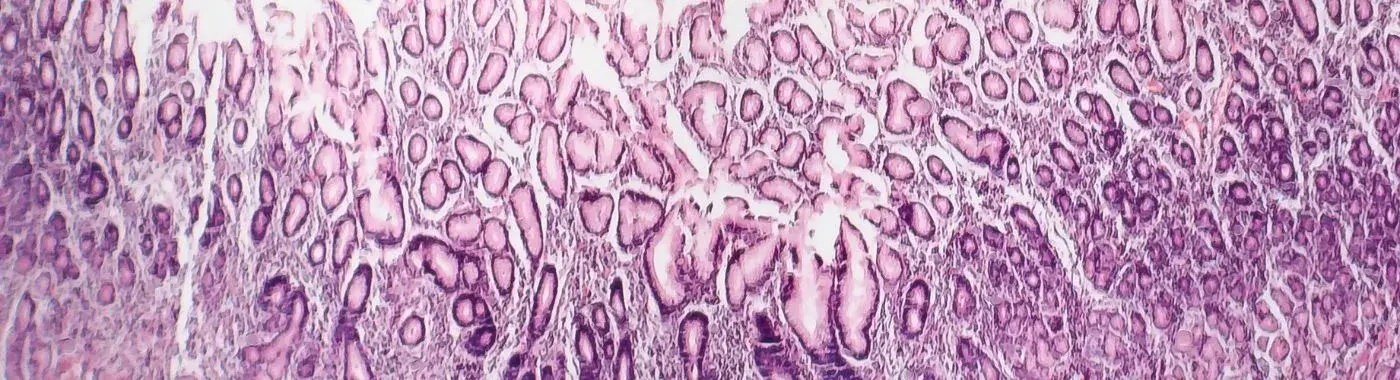

• Biopsy: Tissue samples taken during endoscopy can be examined for signs of atrophy and inflammation.

Atrophic gastritis is defined as a chronic inflammation of the stomach lining that results in the loss of gastric glandular cells. This condition can lead to a decrease in stomach acid production and a reduction in the secretion of digestive enzymes. Atrophic gastritis can be classified into two main types: